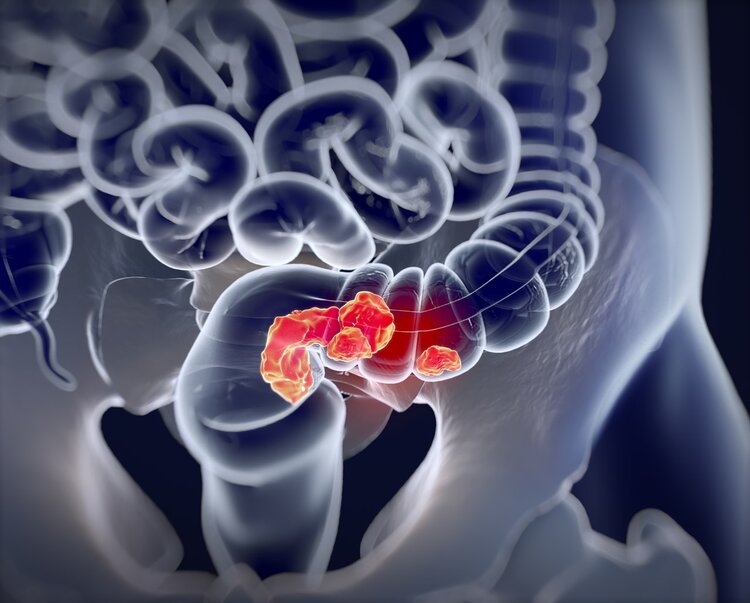

直肠异物会导致血液,直肠粘膜损伤,肛门尿失禁,体重,肠梗阻,肠坏死,肠穿孔和危险生活。从长远来看,还有一个放松的肛门括约肌,并且会有一个击穿和直肠逃生。

当发生肠穿孔时,患者在手术后在肠道手术中开发,并且可能佩戴3-6个月的粪便,然后通过二级手术恢复排便路径。

临床上,直肠异物的类型可以代表五朵花,玻璃瓶,金属管,哈姆森,黄瓜,茄子,麻将,切换,蜡烛和成人玩具。其中,男性患者主要是,男性和女性约37:1。